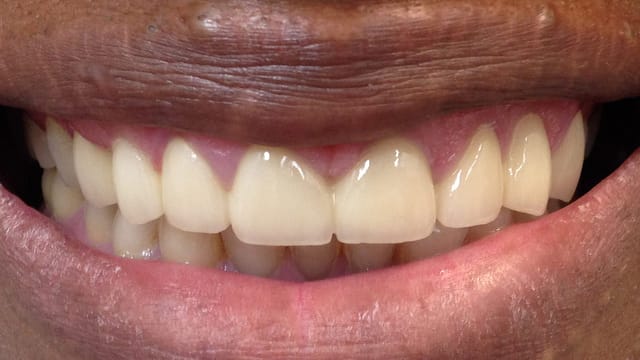

Below is a few examples of what DENTAL IMPLANTS can do for you and your smile!